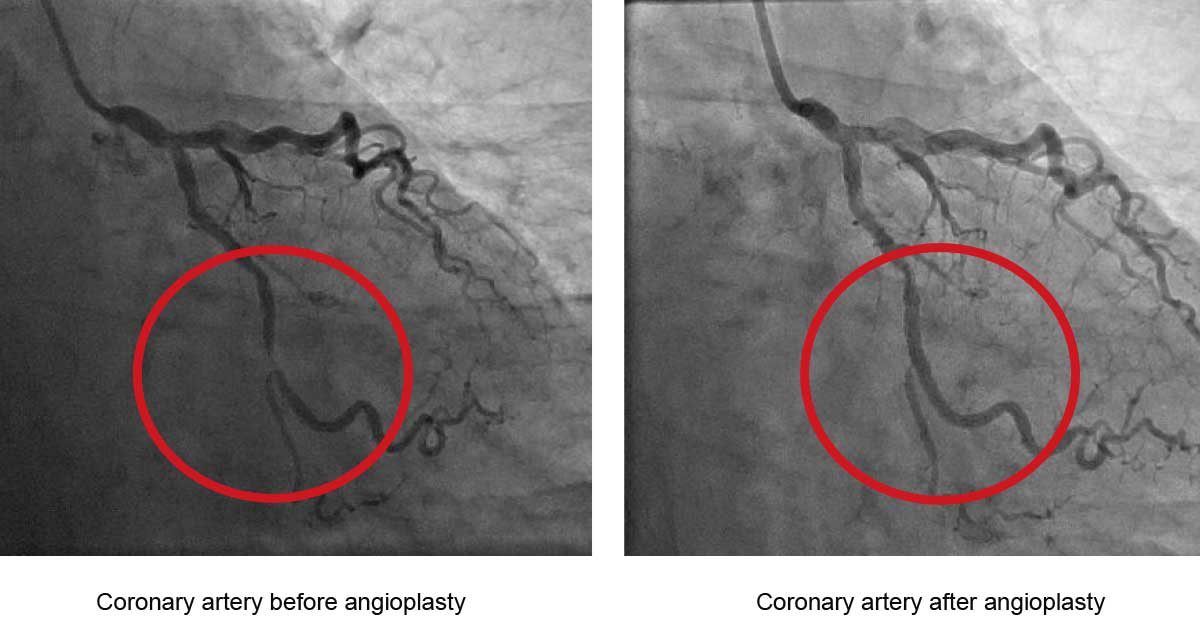

Coronary artery stent: “a small, self-expanding, metal mesh tube. It is placed inside a coronary artery after balloon angioplasty. This stent prevents the artery from re-closing.”

The next day I was second in the queue for an angiogram, followed by an angioplasty. In at 10:30, out by noon, I couldn’t move any part of my body except my head and left arm for four hours after. The artery in question was 80% obstructed, worthy of one stent.